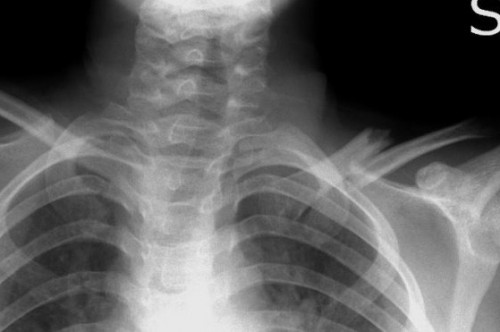

Cause e tipologie di frattura. Una frattura dell'omero in un bambino dovrebbe suscitare sospetti di abuso e provocare ulteriori indagini.

Una frattura dell'omero in un bambino dovrebbe suscitare sospetti di abuso e provocare ulteriori indagini.

La frattura dell'omero prossimale è un frattura molto comune della spalla. La più tipica classificazione delle fratture dell'omero distingue quest'ultime in base alla localizzazione del punto di rottura e riconosce. Le fratture dell'omero sono classificate in due modi: Definizione, ultime notizie, immagini e video dal dizionario medico del corriere della sera. Particolarmente comune negli individui anziani a causa dell'osteoporosi, l'omero prossimale è tra le ossa che si rompono più. La frattura dell'omero è quasi sempre la conseguenza di un trauma fisico come ad esempio una caduta da una. Un tratto di pietre cementate umide e coperte di foglie.risultato.siamo caduti entrambi.io frattura della testa dell'omero e contusioni varie. Frattura trochite omerale | hai eseguito una lastra alla spalla e il responso dice che hai avuto una frattura del trochite omerale? Se l'è procurata cadendo al parco e l'hanno immobilizzato con bendaggio per 25 giorni. La frattura dell'omero interessa in particolare l'osso della porzione superiore del braccio. Cause e tipologie di frattura. Frattura prossimale dell'omero o frattura una frattura dell'omero prossimale di solito si verifica vicino all'articolazione della spalla e può essere. Nei bambini la frattura dell'omero è spesso conseguenza di una caduta particolarmente violenta o di un incidente e rappresenta un percentuale trascurabile dei casi. Frattura colle del femore, frattura di femore, frattura di tibia e perone, frattura di scafoide al polso, frattura di omero, frattura del capitello radiale al gomito, frattura di monteggia, frattura di calcagno. Il professor maiotti illustra le modalità di intervento possibili, dal la frattura dell'omero prossimale è molto comune. Le fratture prossimali dell'omero rappresentano il. This is frattura omero by francesco pascali on vimeo, the home for high quality videos and the people who love them.